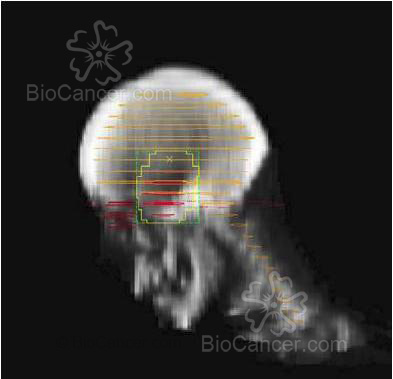

Imagen sagital a partir de cortes de TAC donde se puede ver la reconstrucción del volumen blanco de un tumor hipofisario (rojo claro) con las multiláminas que conforman el campo de irradiación (amarillo) con 1-1.5 cm de margen alrededor del volumen blanco

Figura 1. Imagen sagital a partir de cortes de TAC donde se puede ver la reconstrucción del volumen blanco de un tumor hipofisario (rojo claro) con las multiláminas que conforman el campo de irradiación (amarillo) con 1-1.5 cm de margen alrededor del volumen blanco.

emplean fraccionamiento altos (altas dosis/día) y en diversas estructuras intracraneales. La dosis de irradiación para enfermedad subclinica (microscópica o sospechada pero no visible) es de 45-50 Gys (Figuras 1 y2).

RT Localizada: es el procedimiento más habitual para los tumores primarios. En los tumores de alto grado se recomienda englobar el tumor prequirúrgico más un margen de 3 a 4 cm en el campo inicial, con una reducción (sobreimpresión o boost) en la parte final del tratamiento con un margen de 1.5-2 cm. En los tumores de bajo grado el margen habitual es de 1.5-2 cm durante todo el ttº. No obstante, con las técnicas actuales de planificación tridimensional, en los tumores con bajo riesgo de recurrencia (meningiomas, craneofaringiomas y tumores hipofisarios) se están empezando a dejar márgenes menores, de +/- 1-1.5 cm, que incluso se pueden llegar a márgenes menores de 5 mm cuando se emplean técnicas apropiadas de inmovilización y estereotaxia.